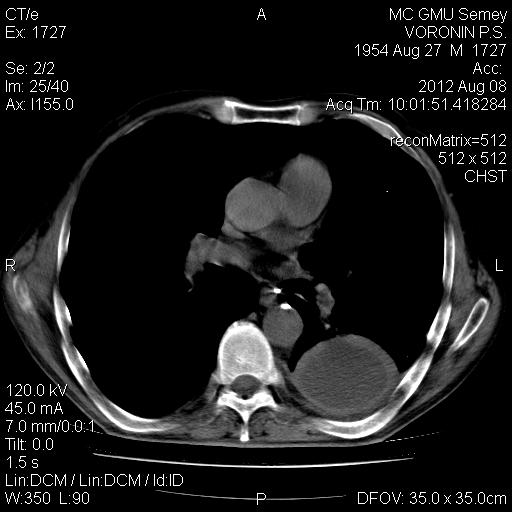

Назовите метод лечения при данной КТ томограмме// противовоспалительная и рассасывающая терапия терапия// +Пункция под УЗИ контролем// Оперативное удаление образования// Оперативное удаление образования и ближайших лимфоузлов// Дренаж плевральной полости по Бюллау

Ваша лечебная тактика при данной КТ картине// противовоспалительная и рассасывающая терапия терапия// Пункция под УЗИ контролем// Оперативное удаление образования// Оперативное удаление образования и ближайших лимфоузлов// +Дренаж плевральной полости